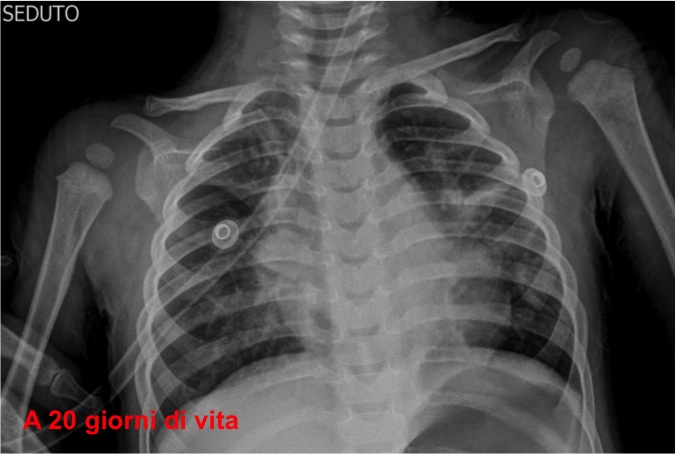

Per il quadro di anemia sideropenica associata a dispnea e infezioni ricorrenti delle basse vie aeree, nel forte sospetto di alveolite emorragica, abbiamo riguardato la storia radiologica della bambina: numerosi Rx torace che mostrano opacit� bilaterale diffusa e aumentata trama interstiziale, sia durante episodi di broncopolmonite che in benessere (Figure 1-4).

Figura 2. Rx effettuata a 20 giorni di vita.